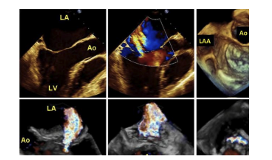

Hình 1: Siêu âm tim 3D-Real-Time (focus exam)

5.1. Siêu âm tim 3D với hình ảnh phóng đại tập trung vào một phần cấu trúc tim (focus exam)

- Đánh giá bộ máy van hai lá, tình trạng van động mạch chủ, đánh giá lỗ thông liên nhĩ.

- Thu nhận hình ảnh 3D bằng kiểu góc quét rộng 90o x 90o quan sát hình ảnh khối kim tự tháp (mode full volume) hoặc quan sát hình ảnh nhỏ, kiểu góc quét nhỏ 30o x 30o (mode zoom) khi người bệnh nín thở. Nếu người bệnh không nín thở được hoặc nhịp tim không đều, sử dụng kiểu thu nhận dữ liệu trong vòng một chu chuyển tim (mode: single-beat) hoặc kiểu góc hẹp (narrow-angle).